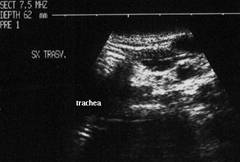

Femeie 17 ani. Voluminoasa tumefactie (32x40x45mm, 29 cc) in lobul stang, intens hipoecogena, cu echo densitati in interior, intarire posterioara. Deviatia tracheei spre dreapta.

Examen citologic; chist coloid